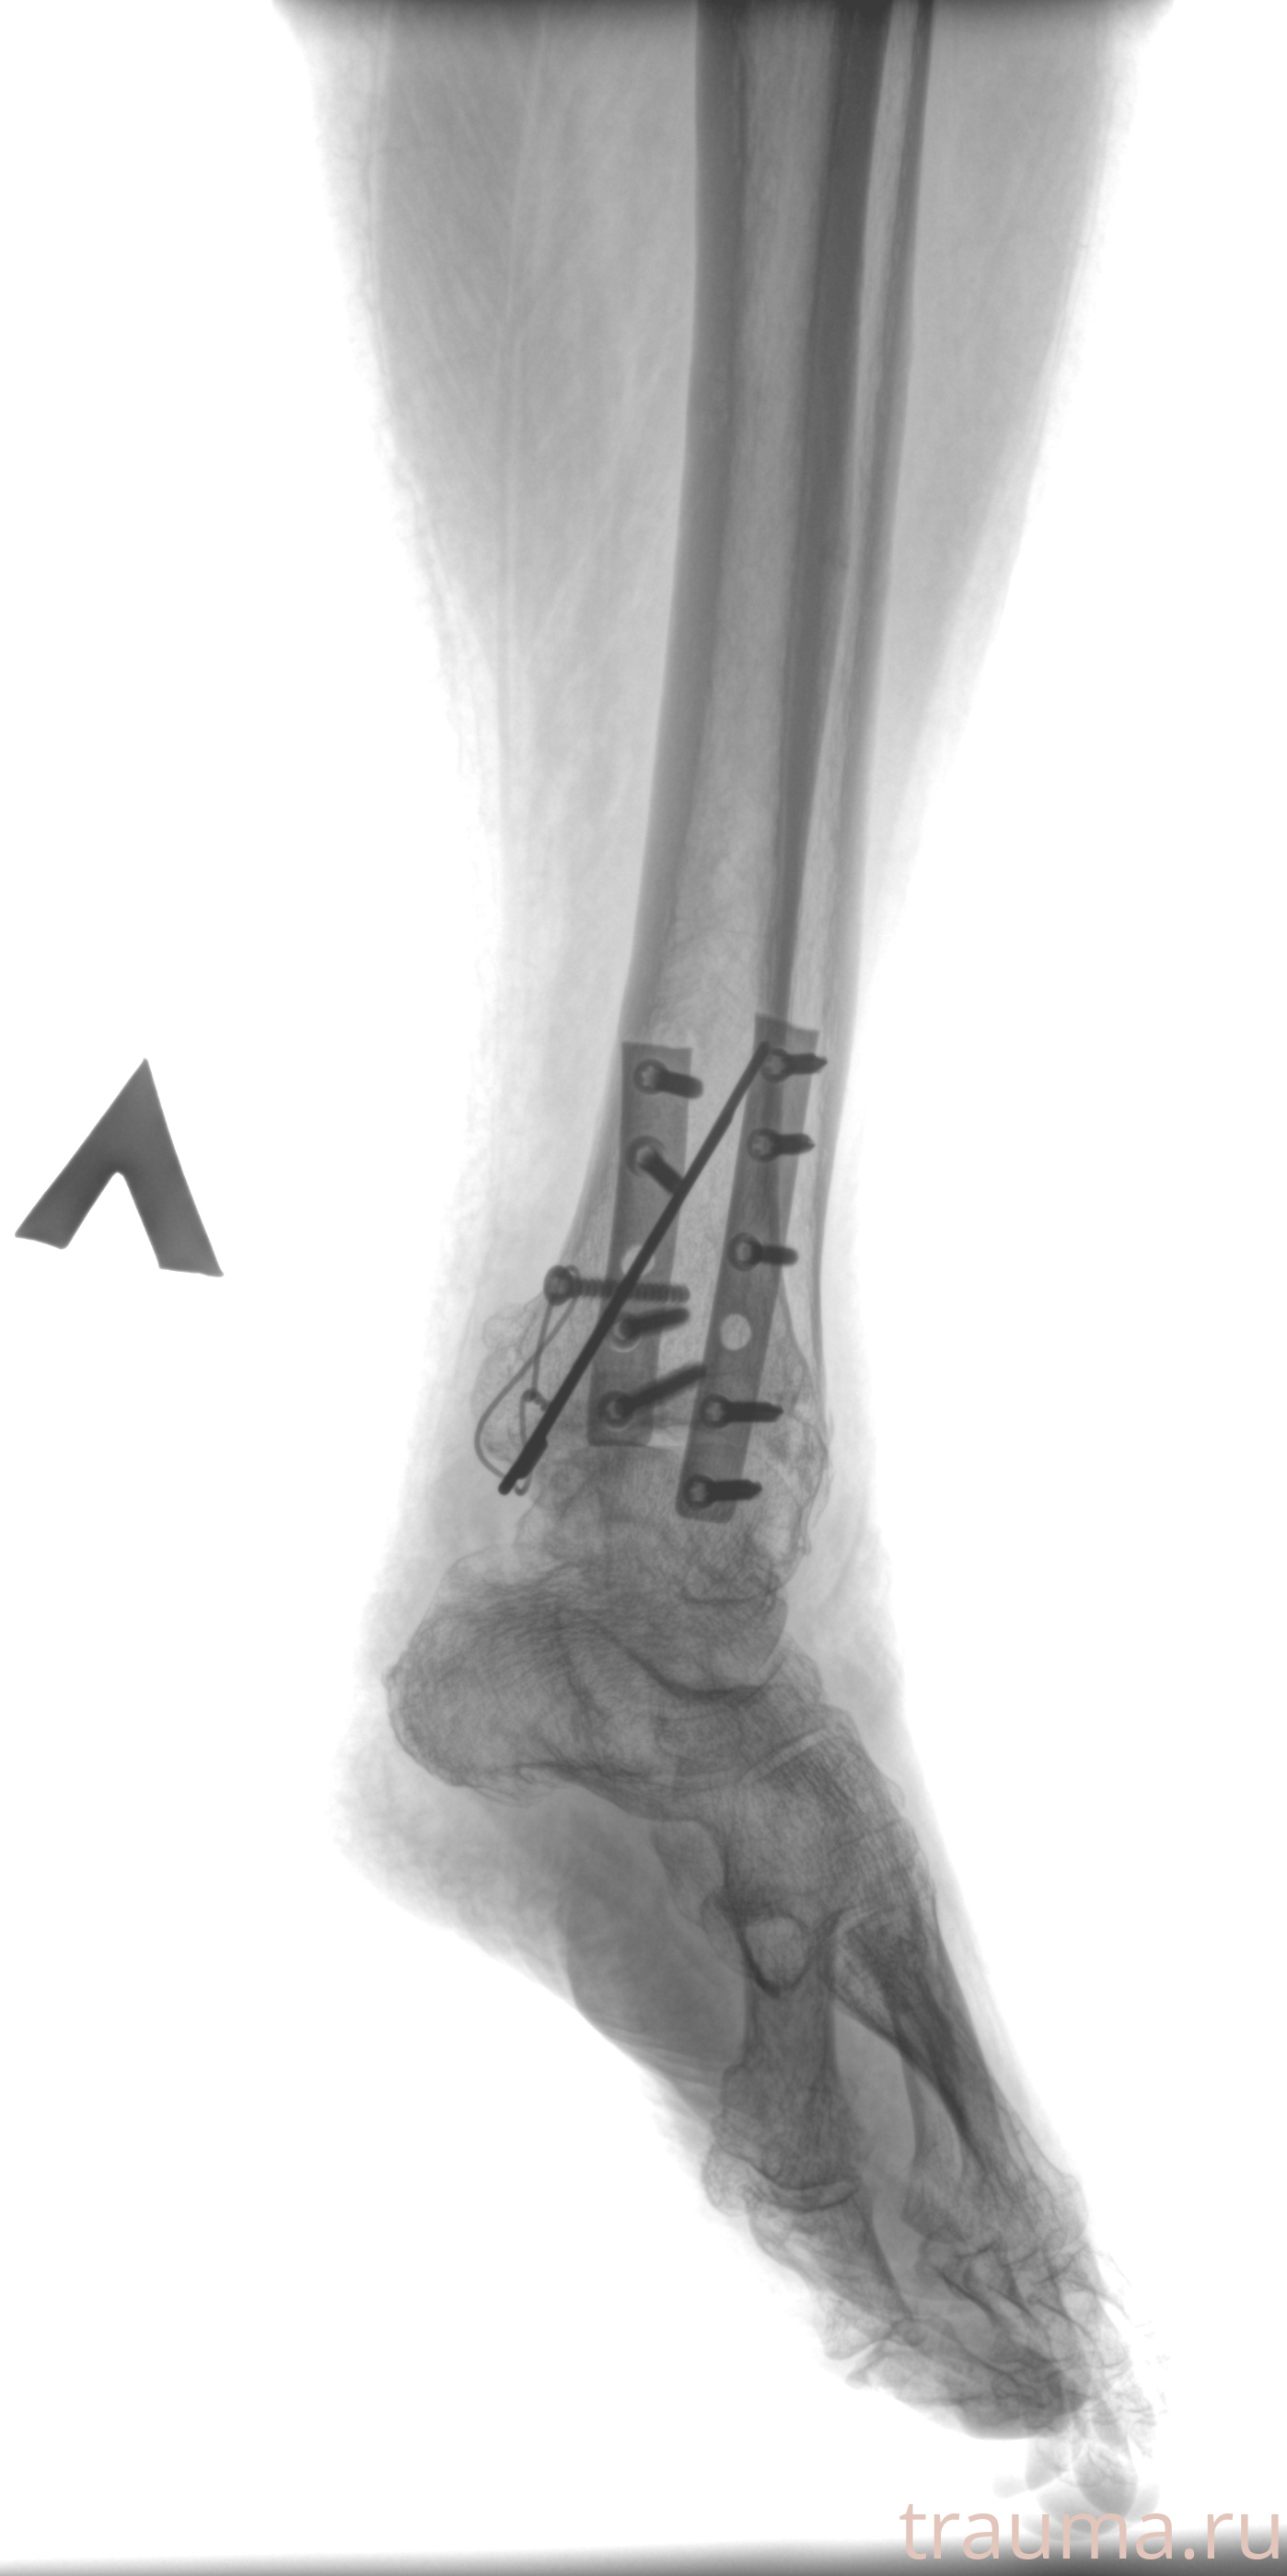

Рентгенограммы